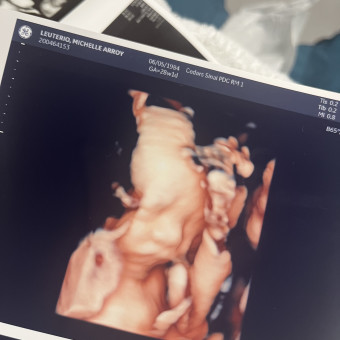

Michelle & Dean Baby Registry

Michelle Leuterio & Dean Kanaloa Sao

March 13, 2025

Thank you for showering baby boy with love ❤️